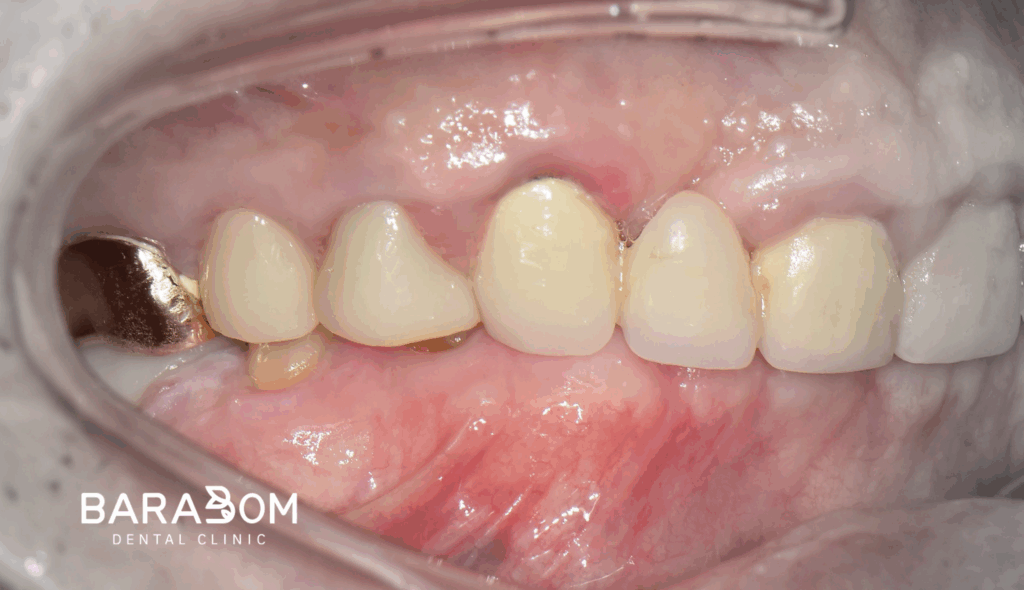

준비한 사진을 보시면, 윗니가 아랫니를 일절 다 덮을 정도로 깊게 물리고 있습니다.

더불어 교합력이 센 탓에 교모가 꽤 심하게 진행되었습니다.

이런 경우, 제가 준비한 케이스처럼 수직 고경이 상실될 수 있습니다.

대개 교모로 인하여 수직 고경이 상실된 케이스를 보면 치관의 길이가 매우 짧습니다. 이런 상태에서 크라운을 씌우게 되면 당연히 안정을 얻기 어렵습니다.

그럼 자주 보철이 탈락하게 되어 불편으로 이어질 수 밖에 없는데, 현재 하악 앞니 뿐만 아니라 어금니도 치아 머리의 길이가 짧은 상태였습니다. 하악 절치부 치관 길이가 매우 짧으며, 상악 절치 구개부와 간격이 불과 2mm 이내였습니다. 현재 상태로써 새로운 보철을 제작하긴 어렵다 판단되고 있습니다.